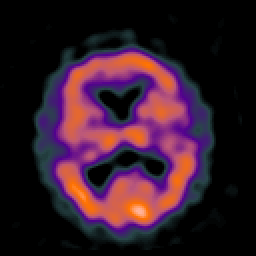

Huntington's Chorea, MR -- Slice #11

[Home][Help][Clinical] Slice 11